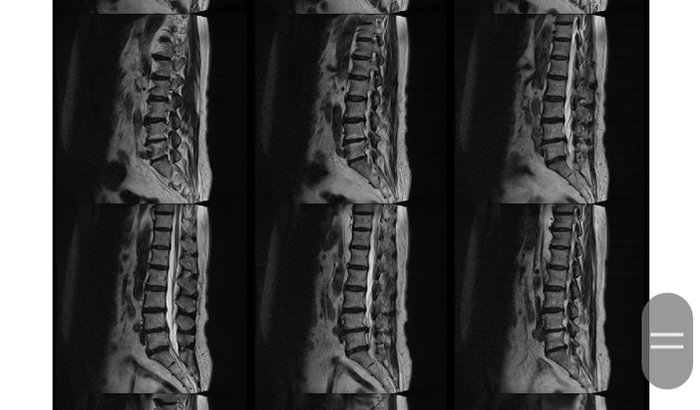

Me chamo Sandra e gostaria de pedir ajuda nas despesas médicas com a saúde da minha mãe. Ela tem 73 anos, não enxerga de uma vista, além de uma certa debilidade na saúde, além dos problemas de coluna que vou relatar. Ela foi diagnosticada com bicos de papagaio e quatro hérnias de disco. Gastamos com várias consultas, exames entre eles ressonância magnética, além de vários medicamentos (muito caros) com valores até de R$267,00 (duas caixas). Além de precisar fazer sessões de fisioterapia e acupuntura, e isso demanda muito dinheiro, além dos gastos que ja tive e estão parcelados no cartão de crédito, e as faturas não esperam. A cada mês chegará á conta. Além do que são dores que vão e vêm. Por isso venho por meio desse site pedir ajuda e colaboração de quem puder. Se cada um puder doar um pouco, vai nos ajudar muito. Com o pouco de muitos, vamos conseguir nossa meta. Deus os abençoe e recompense. https://www.vakinha.com.br/3143702